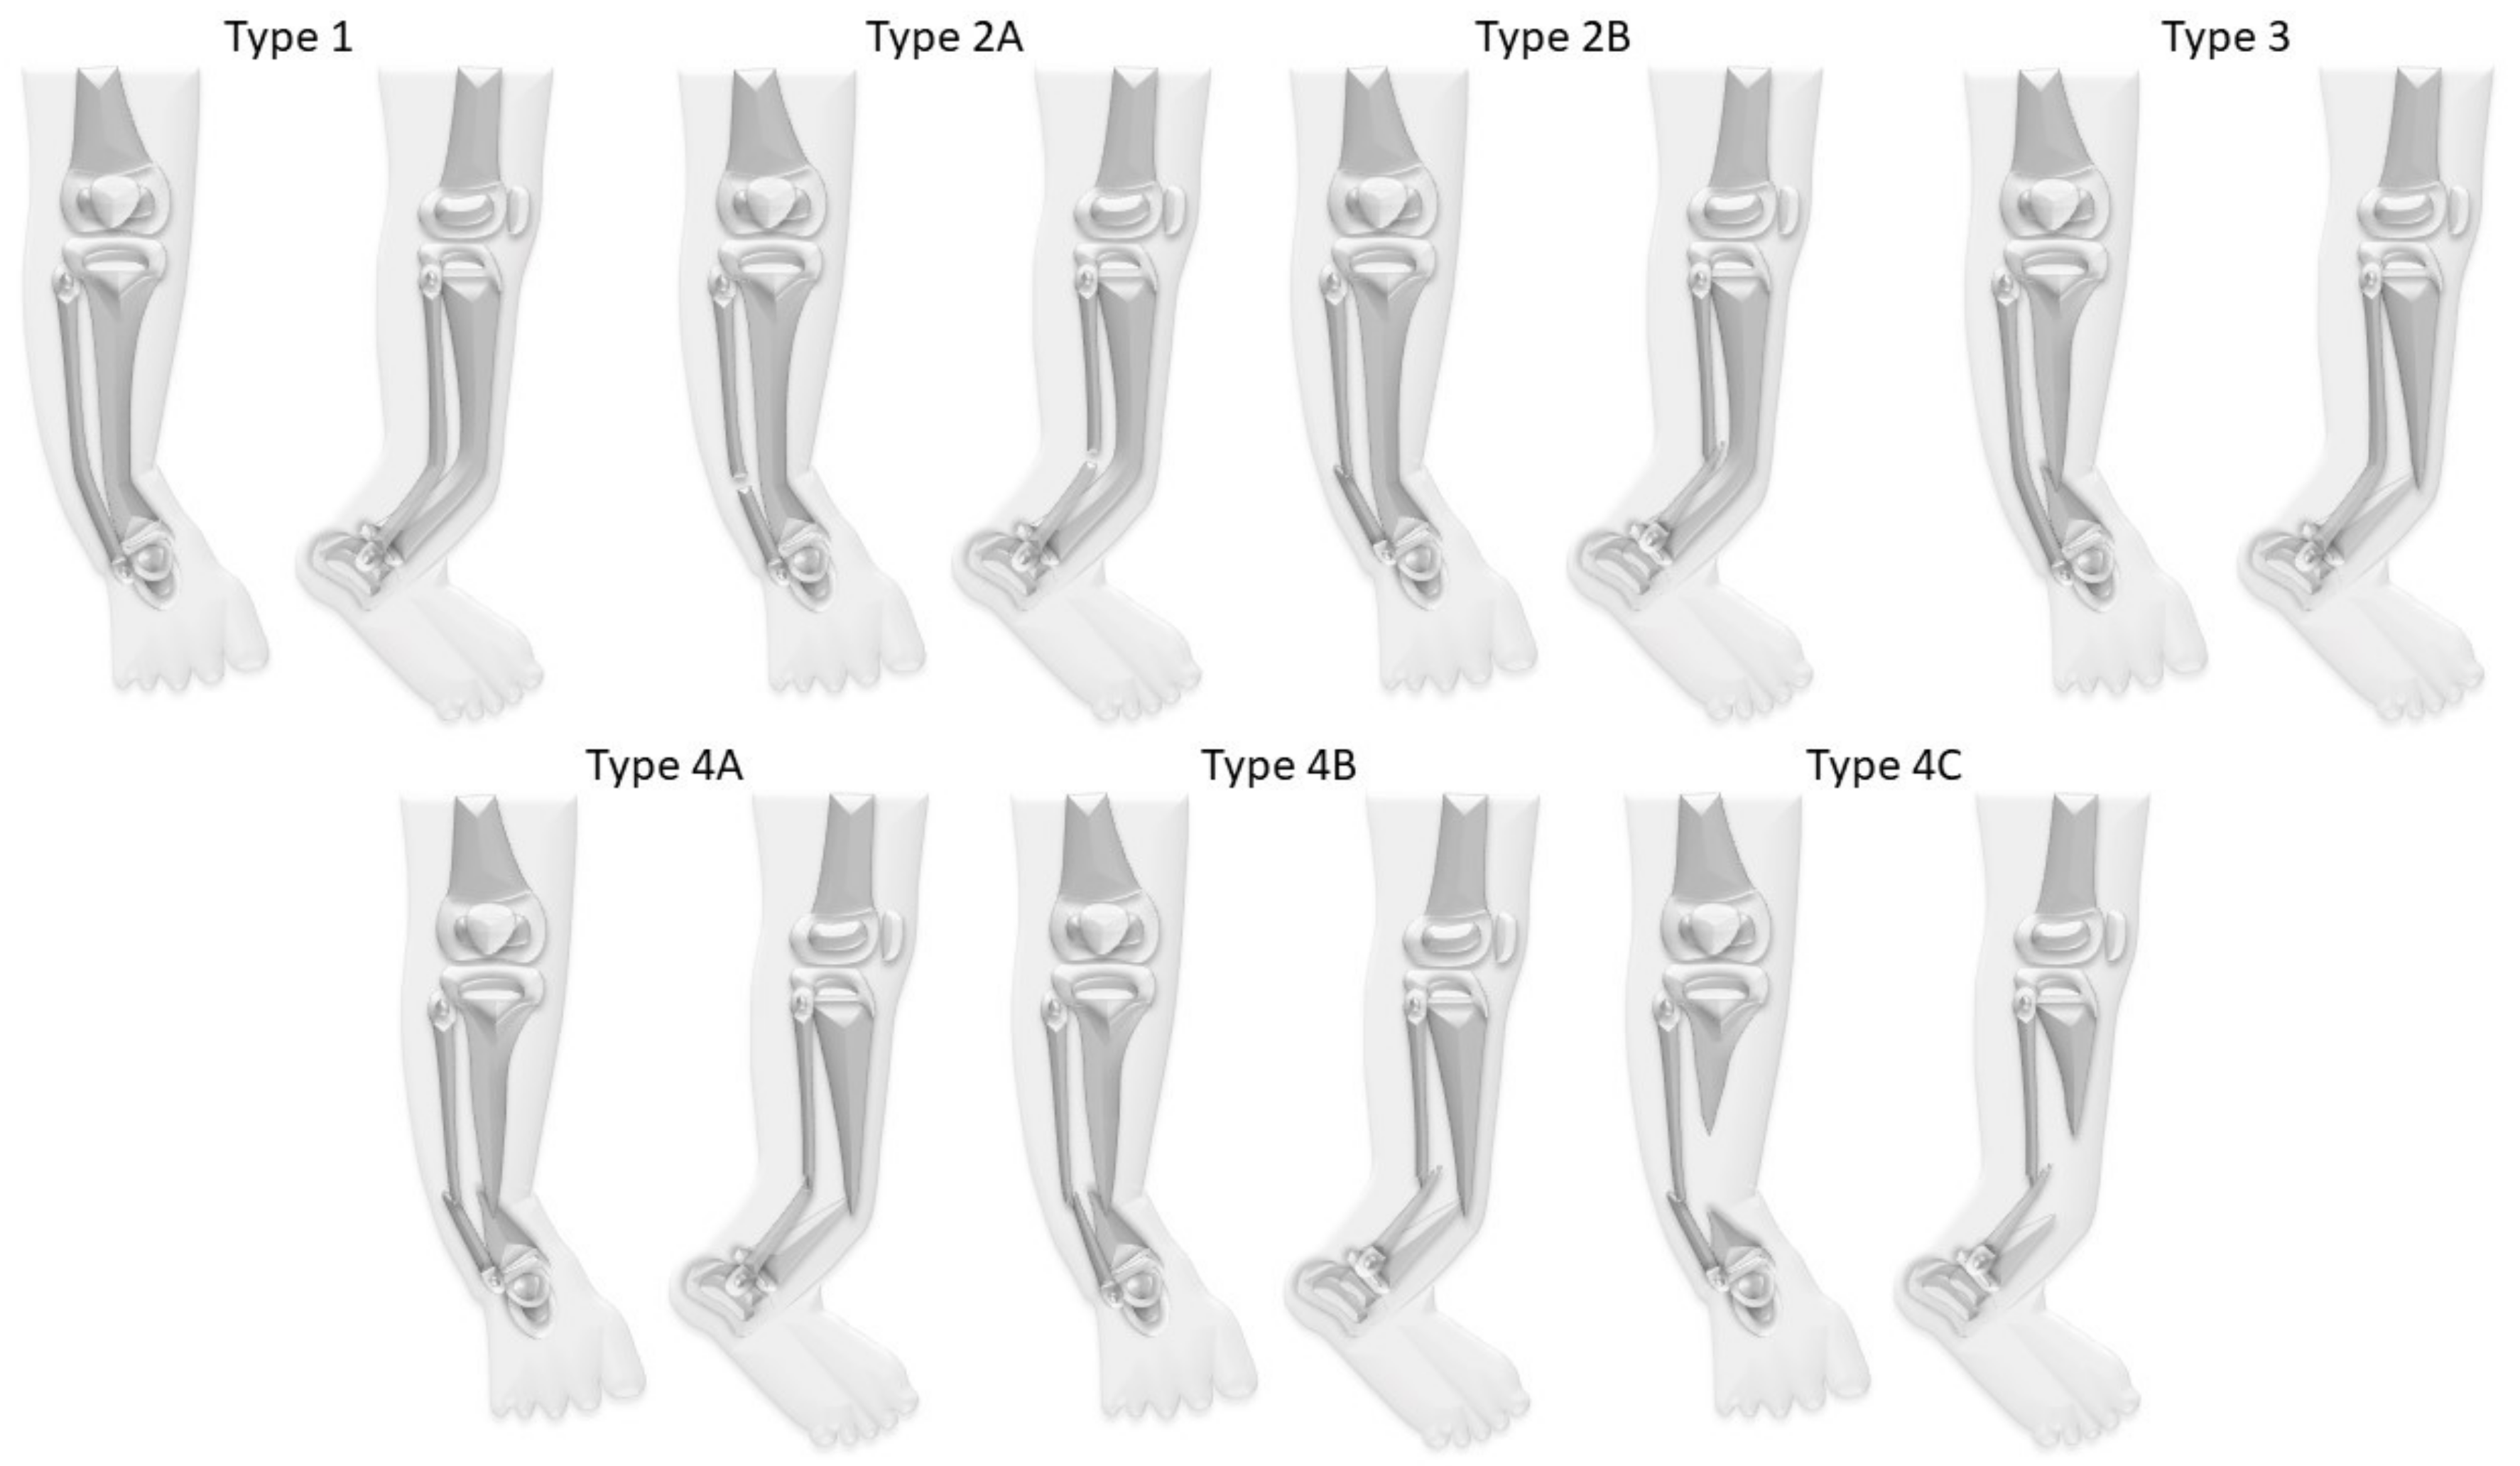

6]. In most cases the pseudarthrosis is not yet present at birth, but the tibia shows a characteristic anterolateral bowing which deteriorates during growth (

Figure 1). A fracture frequently develops spontaneously or after a minor trauma. This leads to a pseudarthrosis with atrophy of the bone ends and a surrounding soft tissue hamartoma impeding physiological healing [

Figure 2) [

8].

Figure 3). Types of CPT were classified according to Paley (

Figure 1,

Table 1,

Table 2 and

Table 3).

In the study cohort CPT was classified according to Paley as follows: Paley type 1 in three patients (12%), type 2A in one patient (4%), type 3 in four patients (15%), type 4A in 16 patients (62%), type 4B in one patient (4%), and type 4C in one patient (4%).